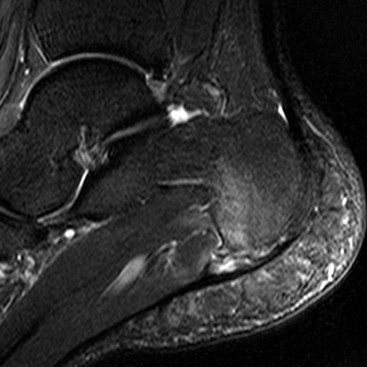

Impingement may occur in various locations around the ankle, the commonest types being anterolateral (see above), anterior and posterior. Anterior impingement occurs between bony spurs on the dorsal talar neck and anterior tibial plafond, a condition associated with kicking activities like soccer. These spurs can be readily identified on lateral radiographs. MRI may additionally reveal synovitis and lateral ankle ligament damage.41 Posterior impingement is most frequently associated with a large os trigonum or Stieda process of the talus (Fig. 46-59). These give rise to chronic compression of soft tissues against the posterior tibia in activities that involve repetitive forced plantar flexion as in ballet dancing.42